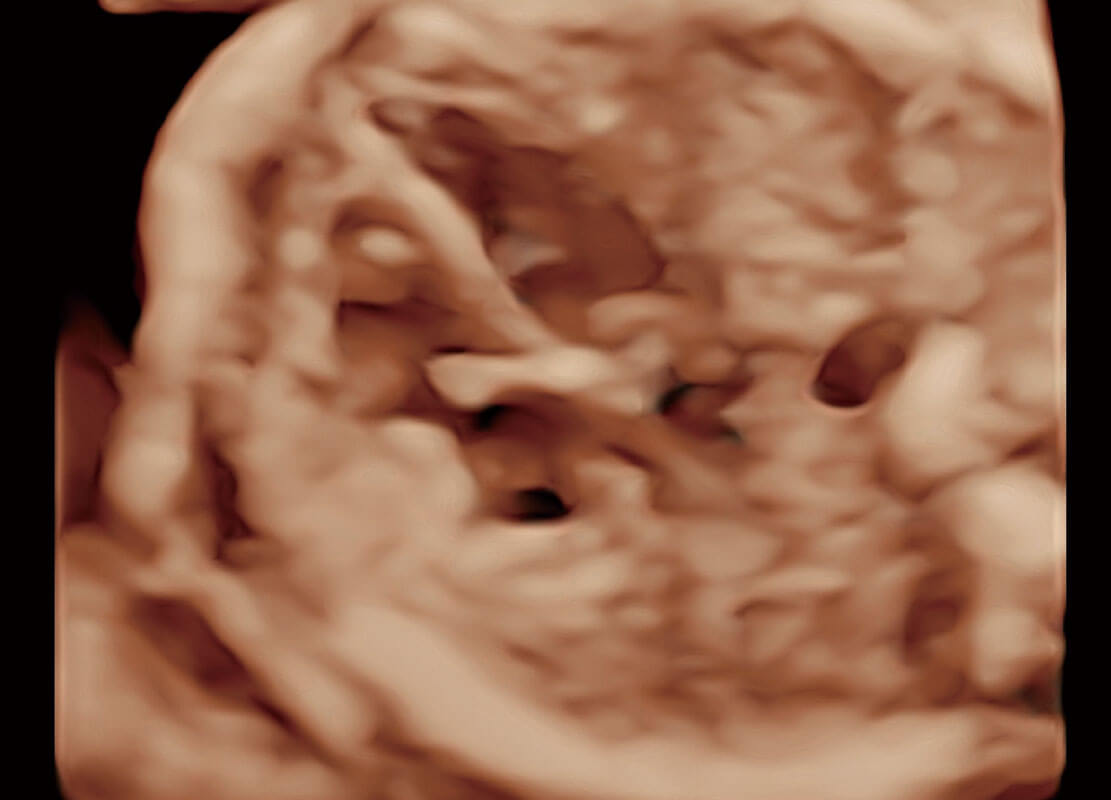

生殖健康

P60优异的图像质量搭载专科探头,在妇科基础疾病的诊断、卵泡生长的监测、输卵管通畅情况的判别等方面为您提供生殖应用方案。

• 腔内妇科-宫腔分离

• 腔内妇科-卵巢

• 腔内三维-宫内节育器

• 腔内三维-光影成像